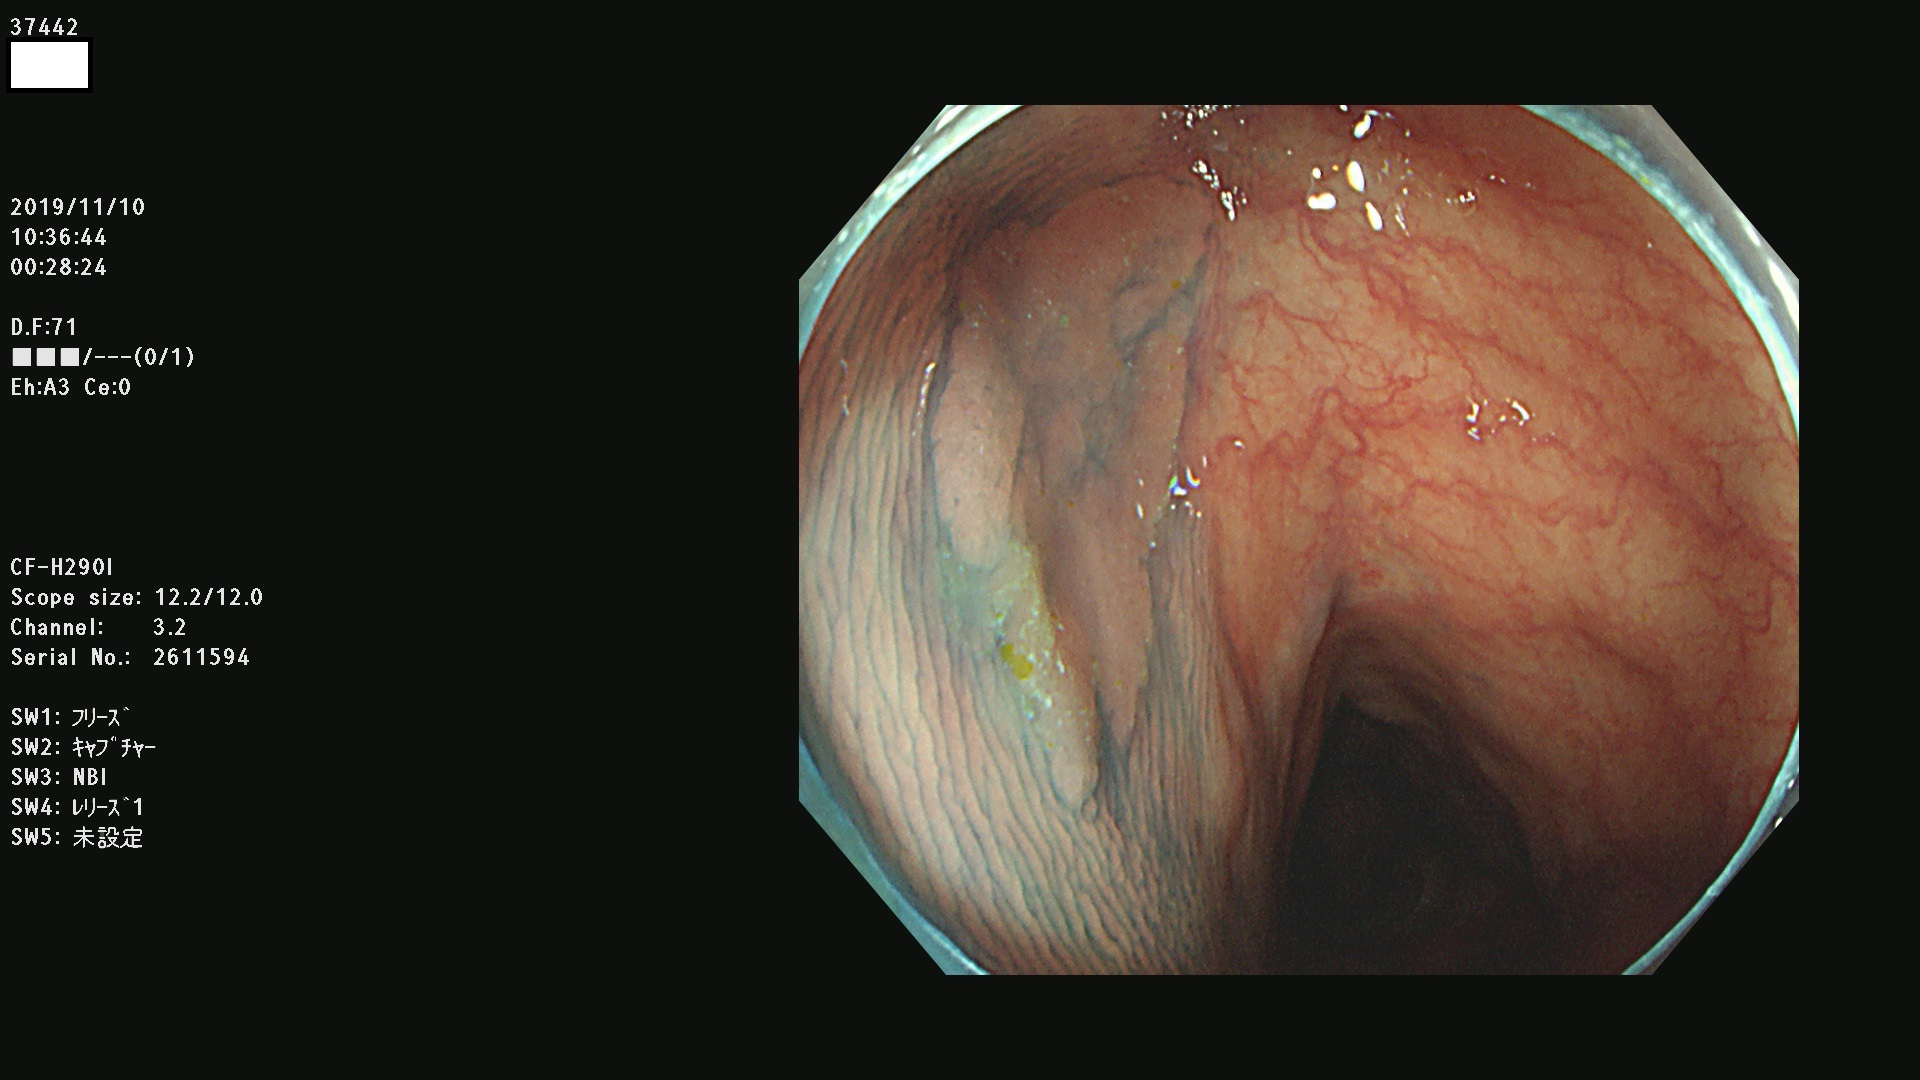

37400(SSAPのみ) 37401 37403 37404 37405 37406 37407 37408 37410 37411 37412 37413 37415 37416 37417 37420 37423 37424 37425 37426 37428 37430(SSAPのみ) 37432 37433 37434 37435 37436 37437 37438 37439 37440 37442 37443 37444 37447 37448 37449 37450 37451 37452 37455 37456 37457 37458 37459 37460 37461 37462 37464 37467 37468 37469 37470(SSAPのみ) 37471 37472 37474 37476(SSAPのみ) 37477 37478 37480 37481 37482 37483 37485 37486 37487 37488 37489 37490 37491 37492 37493 37494 37497 37499

発見困難で危険性の高い平坦型病変(上記100名より抽出)